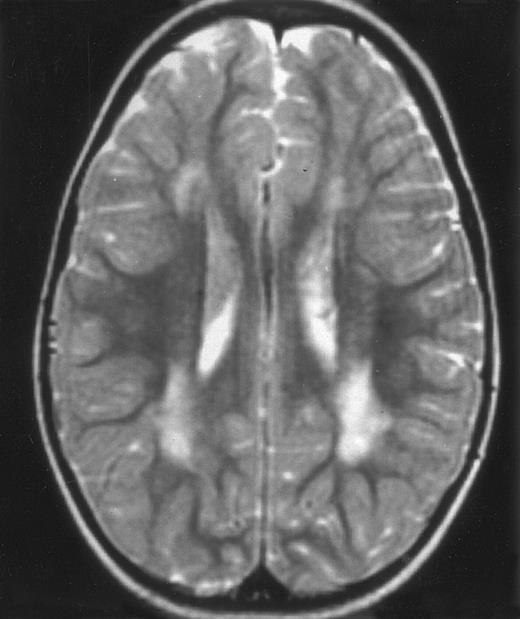

Nine patients were transplanted soon after the remission of initial CNS and systemic manifestations. All of these patients had meningitis only as the CNS manifestation. The median delay between diagnosis and BMT was 4 months (range, 2 to 14 months). Two patients died of BMT-related toxicity (both recipients of an HLA-identical BMT). Seven patients are alive and well with normal neurological examination, normal CSF tap, and normal cognitive development after a follow-up of 18 to 132 months (median, 55 months) (four recipients of an identical BMT and three of a partially-identical BMT). After BMT, chimerism studies demonstrated full or partial engraftment in all of these seven patients. MRI was performed before and after the transplantation in three cases. Two patients had a normal MRI or an isolated subarachnoidal and subdural space dilatation before transplantation and a normal MRI, respectively 4 years and 18 months after transplantation. One patient had white matter abnormalities before transplantation, which remained identical 2 years after transplantation (Fig 4).

MRI of a symptom-free 31/2-year-old child who received BMT at 18 months showing the persistent white matter abnormalities.